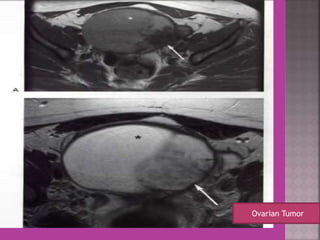

Ovarian Tumor

3. ovarian cancer—malignant versus

benign mass, ascites , retroperitoneal node >

1cm , Bowel bladder , ano rectal . Parietal

peritoneum , liver and or omental

metastasis.